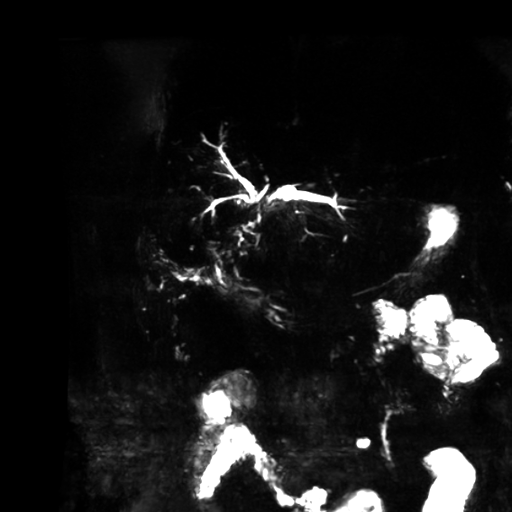

En los últimos años, revisiones y reportes de casos han mostrado con claridad cómo la imagen –especialmente la colangiorresonancia magnética (MRCP)– se ha convertido en la herramienta central para entender esta nueva “normalidad” biliar postquirúrgica y distinguirla de la patología. La MRCP permite mapear con precisión la dilatación de los conductos intrahepáticos, valorar la permeabilidad de la anastomosis, identificar segmentos hepáticos atróficos y orientar el abordaje terapéutico, ya sea endoscópico, percutáneo o quirúrgico.

Recent reviews and case reports have highlighted how imaging—particularly magnetic resonance cholangiopancreatography (MRCP)—has become central to understanding this new postoperative biliary “normal” and distinguishing it from disease. MRCP enables precise mapping of intrahepatic duct dilatation, assessment of anastomotic patency, identification of atrophic liver segments and guidance of therapeutic strategies, whether endoscopic, percutaneous or surgical.

HALLAZGOS IMAGENOLOGICOS

Se observa dilatación de las vías intra hepáticas a expensas de sus ramas hepáticas derecha, anterior y posterior, hepática izquierda y hepática común. El hepático común da la apariencia de estar anastomosado a un asa de intestino, lo que sugiere la posibilidad de una cirugía entero biliar.

No se logra observar el colédoco.

5. Relación imagen–fisiopatología

En la práctica radiológica, esta fisiopatología se traduce en hallazgos como:

o Dilatación segmentaria o difusa de los conductos intrahepáticos proximal a la anastomosis.

o Estrechamiento focal o filiforme en el sitio de la unión bilioentérica.

o Áreas de atrofia hepática con reducción de volumen y remodelado vascular.

o Defectos de llenado compatibles con litos intrahepáticos.

o Signos indirectos de colangitis (engrosamiento de paredes ductales, realce periductal, cambios inflamatorios del parénquima).